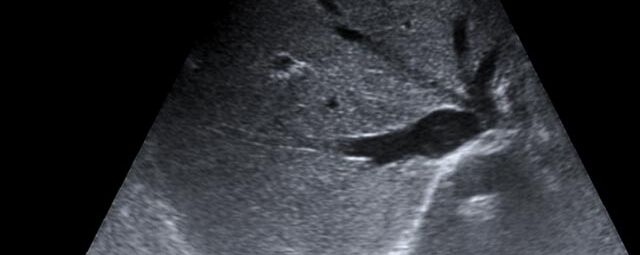

Die Sonographie ist ein bildgebendes Verfahren in der medizinischen Diagnostik, das mit Ultraschallwellen arbeitet. Ultraschall ist Schall mit einer Frequenz oberhalb der menschlichen Hörgrenze. Im medizinischen Bereich werden je nach Körperregion Ultraschallwellen in einem Frequenzbereich von ca. 3,5 – 18 Mhz verwendet. Die körpernahe Ultraschallsonde sendet durch einen piezoelektrischen Effekt kurze Schallwellenimpulse in den Körper. Ultraschall-Gel stellt den Kontakt zwischen Sonde und Körper her. Je nach Gewebeart werden diese Schallwellen im Körper unterschiedlich stark reflektiert. Anhand des zurückgesendeten Schallmusters kann das Ultraschallgerät Schnittbilder berechnen, auf denen die Organe des Körpers nach krankhaften Veränderungen untersucht werden können.

Der Arzt bewegt den Schallkopf mit leichtem Druck in verschiedene Richtungen. Die zu untersuchenden Strukturen können somit aus verschiedenen Perspektiven betrachtet werden. Aussagekräftige Bilder werden festgehalten und digital archiviert, Strukturen oder Organe können zusätzlich vermessen werden. Ein kurzes Befundgespräch erfolgt direkt nach der Untersuchung. Ihr zuweisender Arzt erhält von uns schriftlich einen ausführlichen Befundbericht.